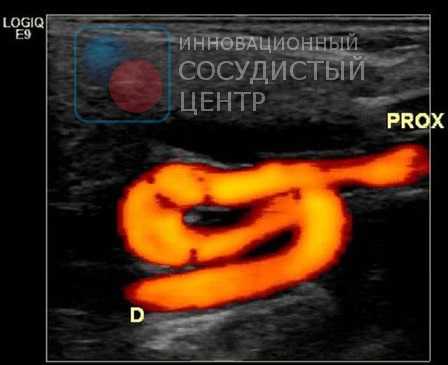

Специалист УЗИ диагностики проводит исследование, располагая ультразвуковой датчик над проекцией магистральных артерий на шее. Датчик посылает ультразвуковые волны в ткани, которые, отражаясь от них, возвращаются в датчик и воспринимаются в виде сигналов аппаратом УЗИ. Так как различные ткани обладают различной способностью поглощать ультразвуковые волны, то и отражённый сигнал будет от них различный, что позволяет дифференцировать их. Кроме исследования отражённого сигнала (В-режим) для оценки кровотока в сосудах используется эффект Доплера, который подразумевает, что скорость отражённого сигнала зависит от скорости объекта, который этот сигнал отражает. Этот эффект позволяет оценить скорость движения эритроцитов в просвете сосуда и составить цветовую карту кровотока. Такой метод называется цветовым допплеровским картированием.

Доктор последовательно изучает УЗИ картину сонных артерий, позвоночных и подключичных артерий. Оценивается проходимость, толщина стенки артерий, форма сосуда и его ход, наличие атеросклеротических бляшек и скорость кровотока по артериям.